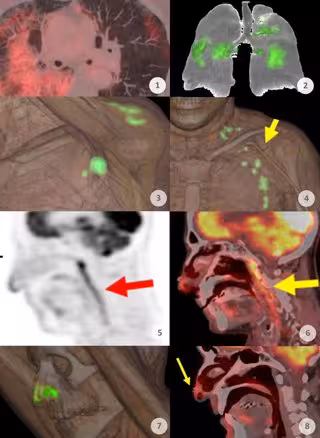

El Servicio de Medicina Nuclear del Hospital Universitario Quirónsalud Madrid, que desde el principio de la pandemia ha estado tratando a sus pacientes sometiéndoles a pruebas de PET-CT, muestra con sus imágenes cómo ha sido la evolución de la pandemia durante estos dos últimos años.

"Durante la primera ola, a partir de marzo de 2020, era muy frecuente observar afectaciones pulmonares. Llegó a apreciarse en el 4 por ciento de todos los pacientes a los que sometemos a pruebas PET", explica el doctor Antonio Maldonado, jefe del Servicio de Medicina Nuclear de Quirónsalud Madrid, que afirma que el COVID-19 no deja de ser una vasculitis sistémica que afectaba a vasos de diferentes niveles.

"Después, con el inicio de la vacunación desde principios de 2021, comenzamos a observar captaciones locales en la zona del hombro con extensión ganglionar, e incluso en el bazo debido a la vacunación. Observamos que en nuestra serie de pacientes la vacuna de Moderna fue la que más reacción producía, que generalmente provocaba también captación en los ganglios adyacentes a la zona de vacunación", añade.

En cambio, con la llegada y generalización de la variante ómicron a finales de 2021 se ha observado un cambio de patrón. "Ya no observamos afectaciones pulmonares como en la primera ola, sino que se aprecian con frecuencia captaciones en las mucosas oro y nasofaríngeas. Este nuevo patrón lo observamos desde diciembre de 2021", afirma.

Aparte del interés de observar cómo el PET-TC ha ido mostrando la evolución de la epidemia de la COVID-19, la difusión de estos hallazgos es importante para "que los médicos nucleares conozcan qué se están produciendo y valoren adecuadamente la presencia de estas captaciones en las imágenes para no alarmar innecesariamente al oncólogo, al paciente y para evitar procedimientos invasivos al paciente que no son necesarios. Es importante manifestar claramente en los informes que estos hallazgos son benignos para que no alteren el tratamiento de estos pacientes", analiza el doctor Maldonado que cree que la imagen PET ha puesto de manifiesto cómo iba evolucionando la pandemia, dando información de lo que estaba sucediendo dentro del cuerpo de los enfermos.

El último hallazgo que ha alimentado la curiosidad del equipo de Medicina Nuclear son las captaciones en la punta de la nariz de muchos enfermos "Los denominados hallazgos de superficie de anclaje nasal. Creemos que muestra actividad producida por el ajuste de la mascarilla con la mano, pero aún no estamos seguros porque no la habíamos visto con tanta frecuencia hace unos meses cuando también se utilizaba la mascarilla. Debemos seguir estudiando", explica.